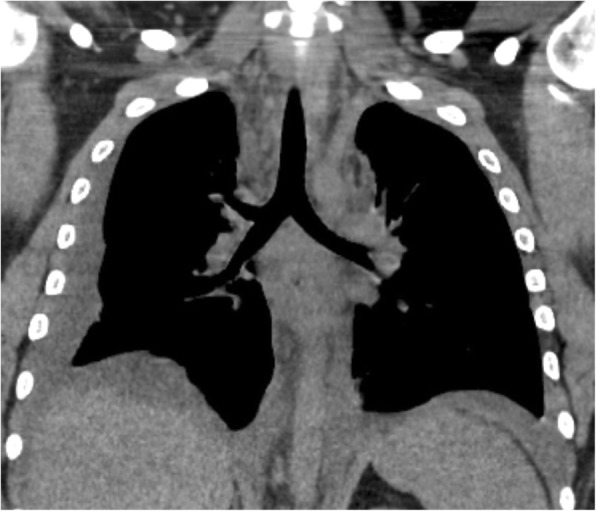

Blood tests were consistent with a marked inflammatory syndrome with a high leucocytes level (41,000 /mm3; 82% of neutrophils) and a CRP of 450 mg/l. Procalcitonin was 3.3 ng/ml and lactate was 1.31 mmol/l. Neck and chest CT-scan revealed an enlargement of the mediastinum due to a diffuse mediastinal infiltration with a moderate bilateral pleural effusion (Fig. 1), without lung parenchymal, pharyngeal and neck abnormalities or jugular venous thrombosis. Esophageal perforation was ruled out by a Barium swallow test and esophagogastroduodenoscopy. Community-acquired mediastinitis being suspected, empirical antibiotic treatment with intravenous amoxicillin/clavulanic acid 1 g q.i.d. was started in the ED and the patient was transferred in the intensive care unit (ICU).

Fig. 1.

Chest CT scan of the initial presentation of the mediastinitis, with diffuse mediastinal infiltration